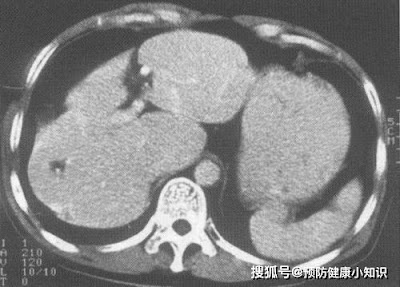

Bà Lý (Trung Quốc), năm nay 56 tuổi, chủ yếu làm nội trợ. Bà được chẩn đoán mắc bệnh ung thư gan giai đoạn cuối, hiện đã không thể tiếp tục điều trị.

Cách đây vài tháng, bà Lý bị vàng da nặng và đau tức vùng bụng bên phải. Lúc đầu, bà Lý không quan tâm lắm nhưng cơn đau bụng ngày càng nhiều, ảnh hưởng nghiêm trọng đến sinh hoạt hằngngày. Bà cùng chồng vào viện khám.

Sau khi có kết quả, cả hai chết lặng, bà Lý được chẩn đoán mắc bệnh ung thư gan. Bà Lý hoang mang vì chưa bao giờ hút thuốc hay uống rượu, không hiểu tại sao lại bị ung thư gan.

Sau khi bác sĩ tìm hiểu thói quen sinh hoạt của bà Lý, ông mới phát hiện ra nguyên nhân thực ra là do 3 vật dụng trong bếp lâu ngày không được vệ sinh.

Sau đó, chồng và các con của bà Lý cũng đã đi khám và phát hiện ra các mức độ khác nhau của bệnh viêm gan vi rút.